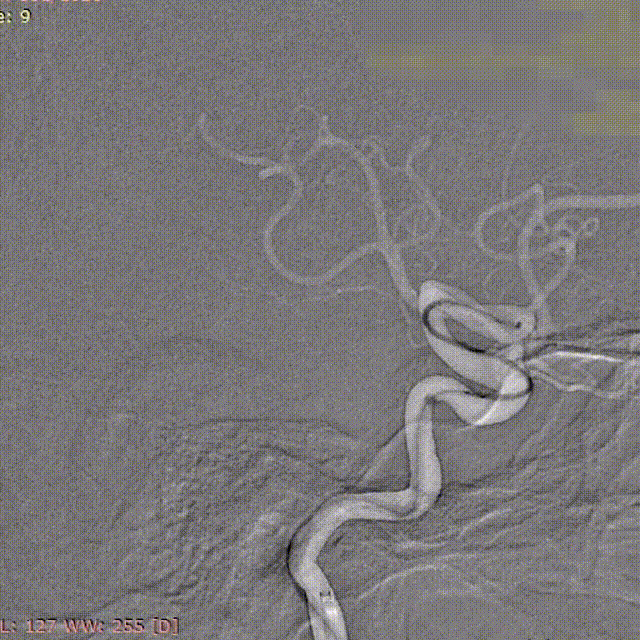

浦奔放教授病例分享二:右侧椎动脉夹层动脉瘤

患者:男性,50岁。

主诉:患者自诉于两周前无明显诱因出现头痛,以右侧枕部胀痛为主,休息后缓解。

颈部CTA提示:右侧V4近段及中上段、右侧V4中上段管腔中-重度狭窄,动脉夹层可能。

左侧椎动脉:

右侧椎动脉(劣势):

左侧椎动脉劣势,颅内段纤细;右侧V4段夹层,血管狭窄。

载瘤动脉远端血管直径:1.50mm

载瘤动脉近端血管直径:1.83mm

2mm*20mm 强易达(Choydar)血流导向密网支架

3mm*25mm 强易达(Choydar)血流导向密网支架

微导丝带017 Accessway微导管上高至远端。

第一枚2*20支架通过017支架微导管到位。

支架远端打开。

支架远端打开情况。

支架中段打开,过50%释放标记点。

造影显示支架整体打开良好。

支架完全释放。

微导管沿推送杆通过支架,撤出推送杆,保留通路。

造影显示支架打开良好,准备桥接第二枚支架。

第二枚3*25支架沿017支架微导管上高。

第二枚支架远端释放。

第二枚支架释放至中段。

中段释放适当推挤系统,保持贴壁良好。

中段释放后造影。

继续释放支架。

继续释放支架,造影观察贴壁良好。

完全释放支架。

支架微导管沿推送导丝上高并将推送导丝撤出。

术后即刻造影。

术后重建。